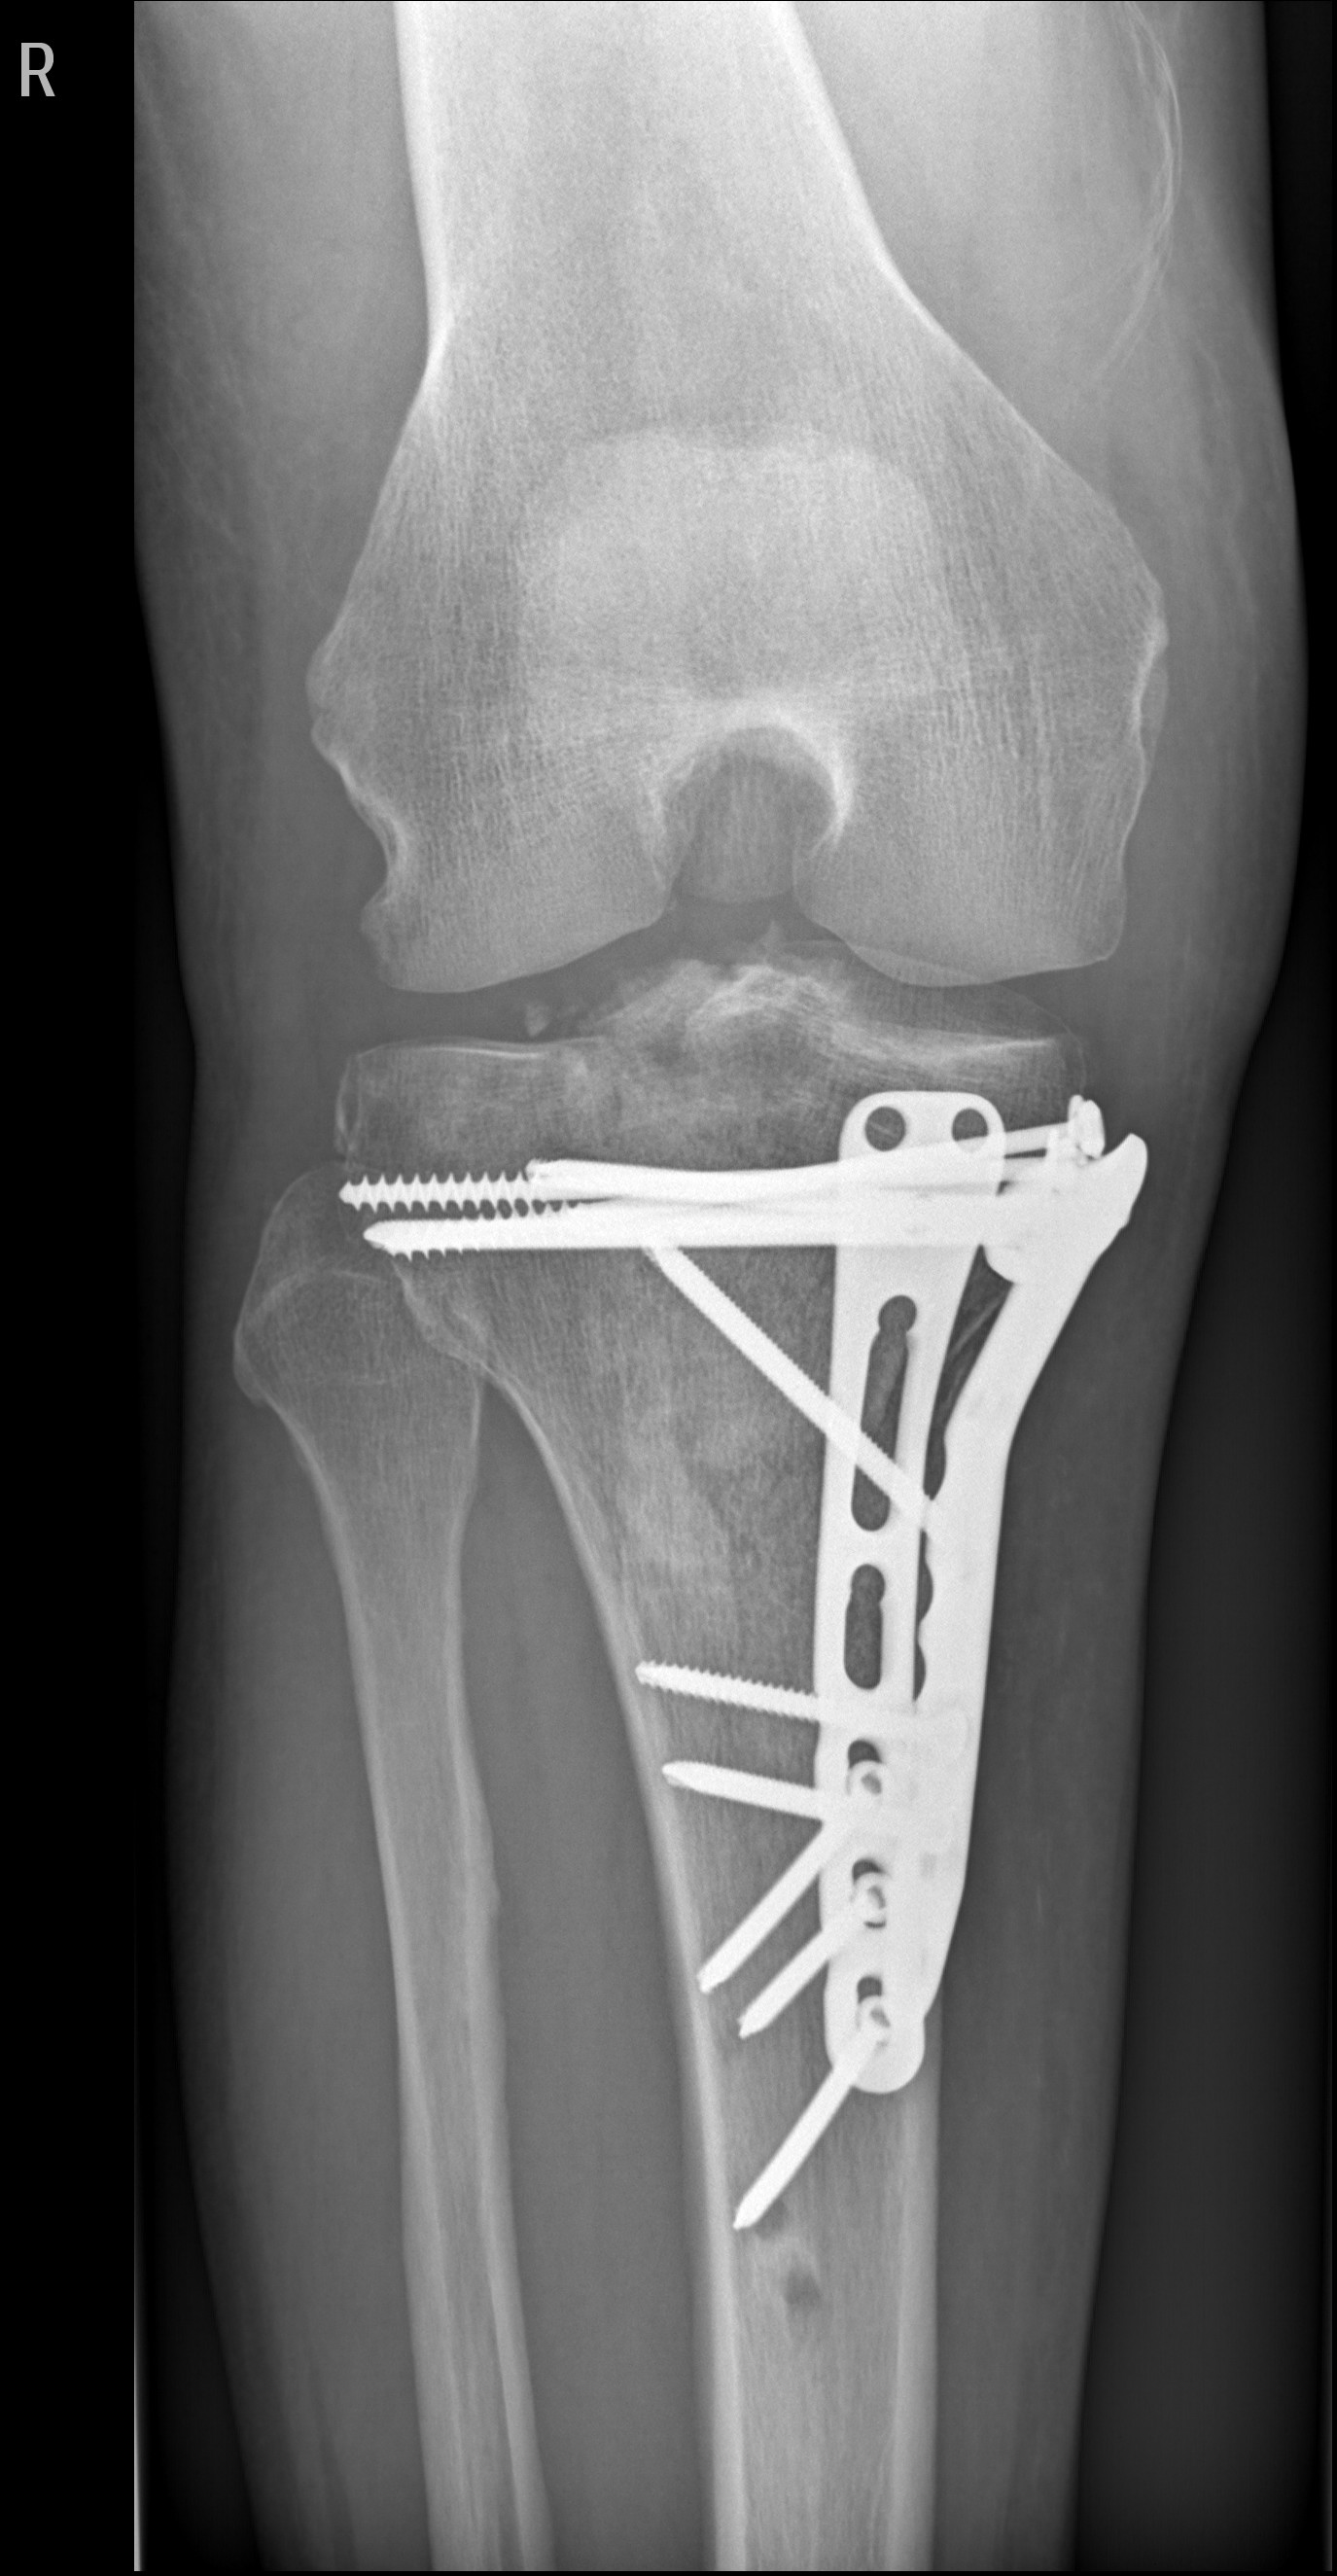

Lange Rede, kurzer Sinn, Schienbein rechts innen durch den Zylinder zerschmettert!

Erstes O.P. Externer Fixateur,

Zweiter O.P.-Bissjen titanium.

Anhang anzeigen 427376

Anhang anzeigen 427377

Die Stangen Aussen - Fixateur extern - fixieren die Fraktur vor bzw. bis zur eigentlichen OP, Schwellung muss runter usw.

Die Schrauben / Plattenosthesynthese fixiert die Fraktur von Innen.

Manches Material entfernt man nach bis zu einem Jahr, manches bleibt dauerhaft drin. Je nach Befund.